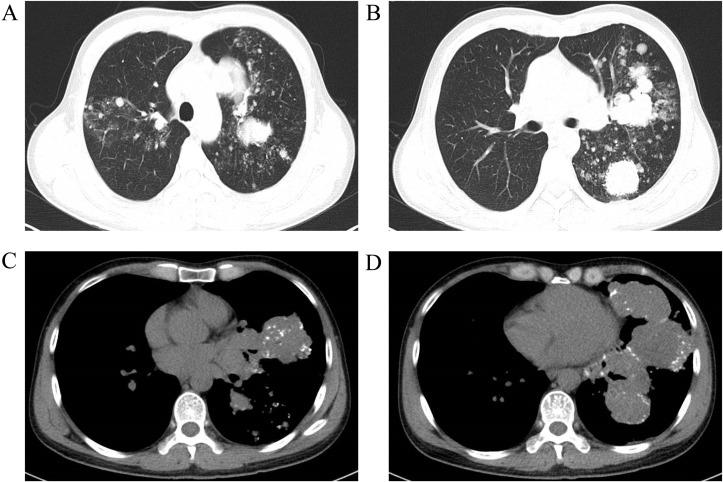

Pulmonary mucinous epithelioid carcinoma (PMEC) is a rare malignancy that typically progresses slowly and has a favorable prognosis. In contrast, adrenal sarcomatoid carcinoma (ASC) is an aggressive and uncommon cancer with poor outcomes. The coexistence of low-grade PMEC and metastatic ASC is exceedingly rare and presents unique clinical challenges, with limited treatment options and poor prognosis. This case report highlights the diagnosis and management of a patient with long-term, slow-progressing low-grade PMEC and rapidly progressing metastatic ASC.

CASE PRESENTATION

A 44-year-old male with a 20-year history of intermittent respiratory symptoms developed abdominal pain and imaging findings indicative of adrenal metastasis and multiple bone metastases. Initial diagnosis through CT and PET-CT scans raised suspicion for pulmonary tumors, and subsequent biopsies confirmed low-grade PMEC in the lungs. In 2023, further diagnostic work revealed a sarcomatoid carcinoma (SC) in the left adrenal gland. Molecular testing revealed BRAF p.V600E mutations across lung, adrenal, and plasma samples, providing critical insight into the nature of the metastatic spread. Despite treatment with molecular therapy (dabrafenib + trametinib) and radiotherapy, the patient's conditioan deteriorated rapidly, and he passed away in September 2023.

肺黏液性上皮样癌(PMEC)是一种罕见的恶性肿瘤,通常进展缓慢,预后良好。相比之下,肾上腺肉瘤样癌(ASC)是一种侵袭性强且罕见的癌症,预后较差。低级别PMEC与转移性ASC共存极为罕见,带来了独特的临床挑战,治疗选择有限且预后不良。本病例报告重点介绍了一名患有长期、进展缓慢的低级别PMEC和快速进展的转移性ASC患者的诊断和治疗情况。

病例介绍

一名44岁男性,有20年间歇性呼吸道症状病史,出现腹痛,影像学检查发现肾上腺转移和多处骨转移。通过CT和PET-CT扫描初步诊断怀疑肺部有肿瘤,随后活检证实肺部为低级别PMEC。2023年,进一步诊断发现左肾上腺有肉瘤样癌(SC)。分子检测显示肺、肾上腺和血浆样本中均存在BRAF p.V600E突变,为转移扩散的性质提供了关键见解。尽管接受了分子治疗(达拉非尼+曲美替尼)和放疗,患者病情仍迅速恶化,于2023年9月去世。